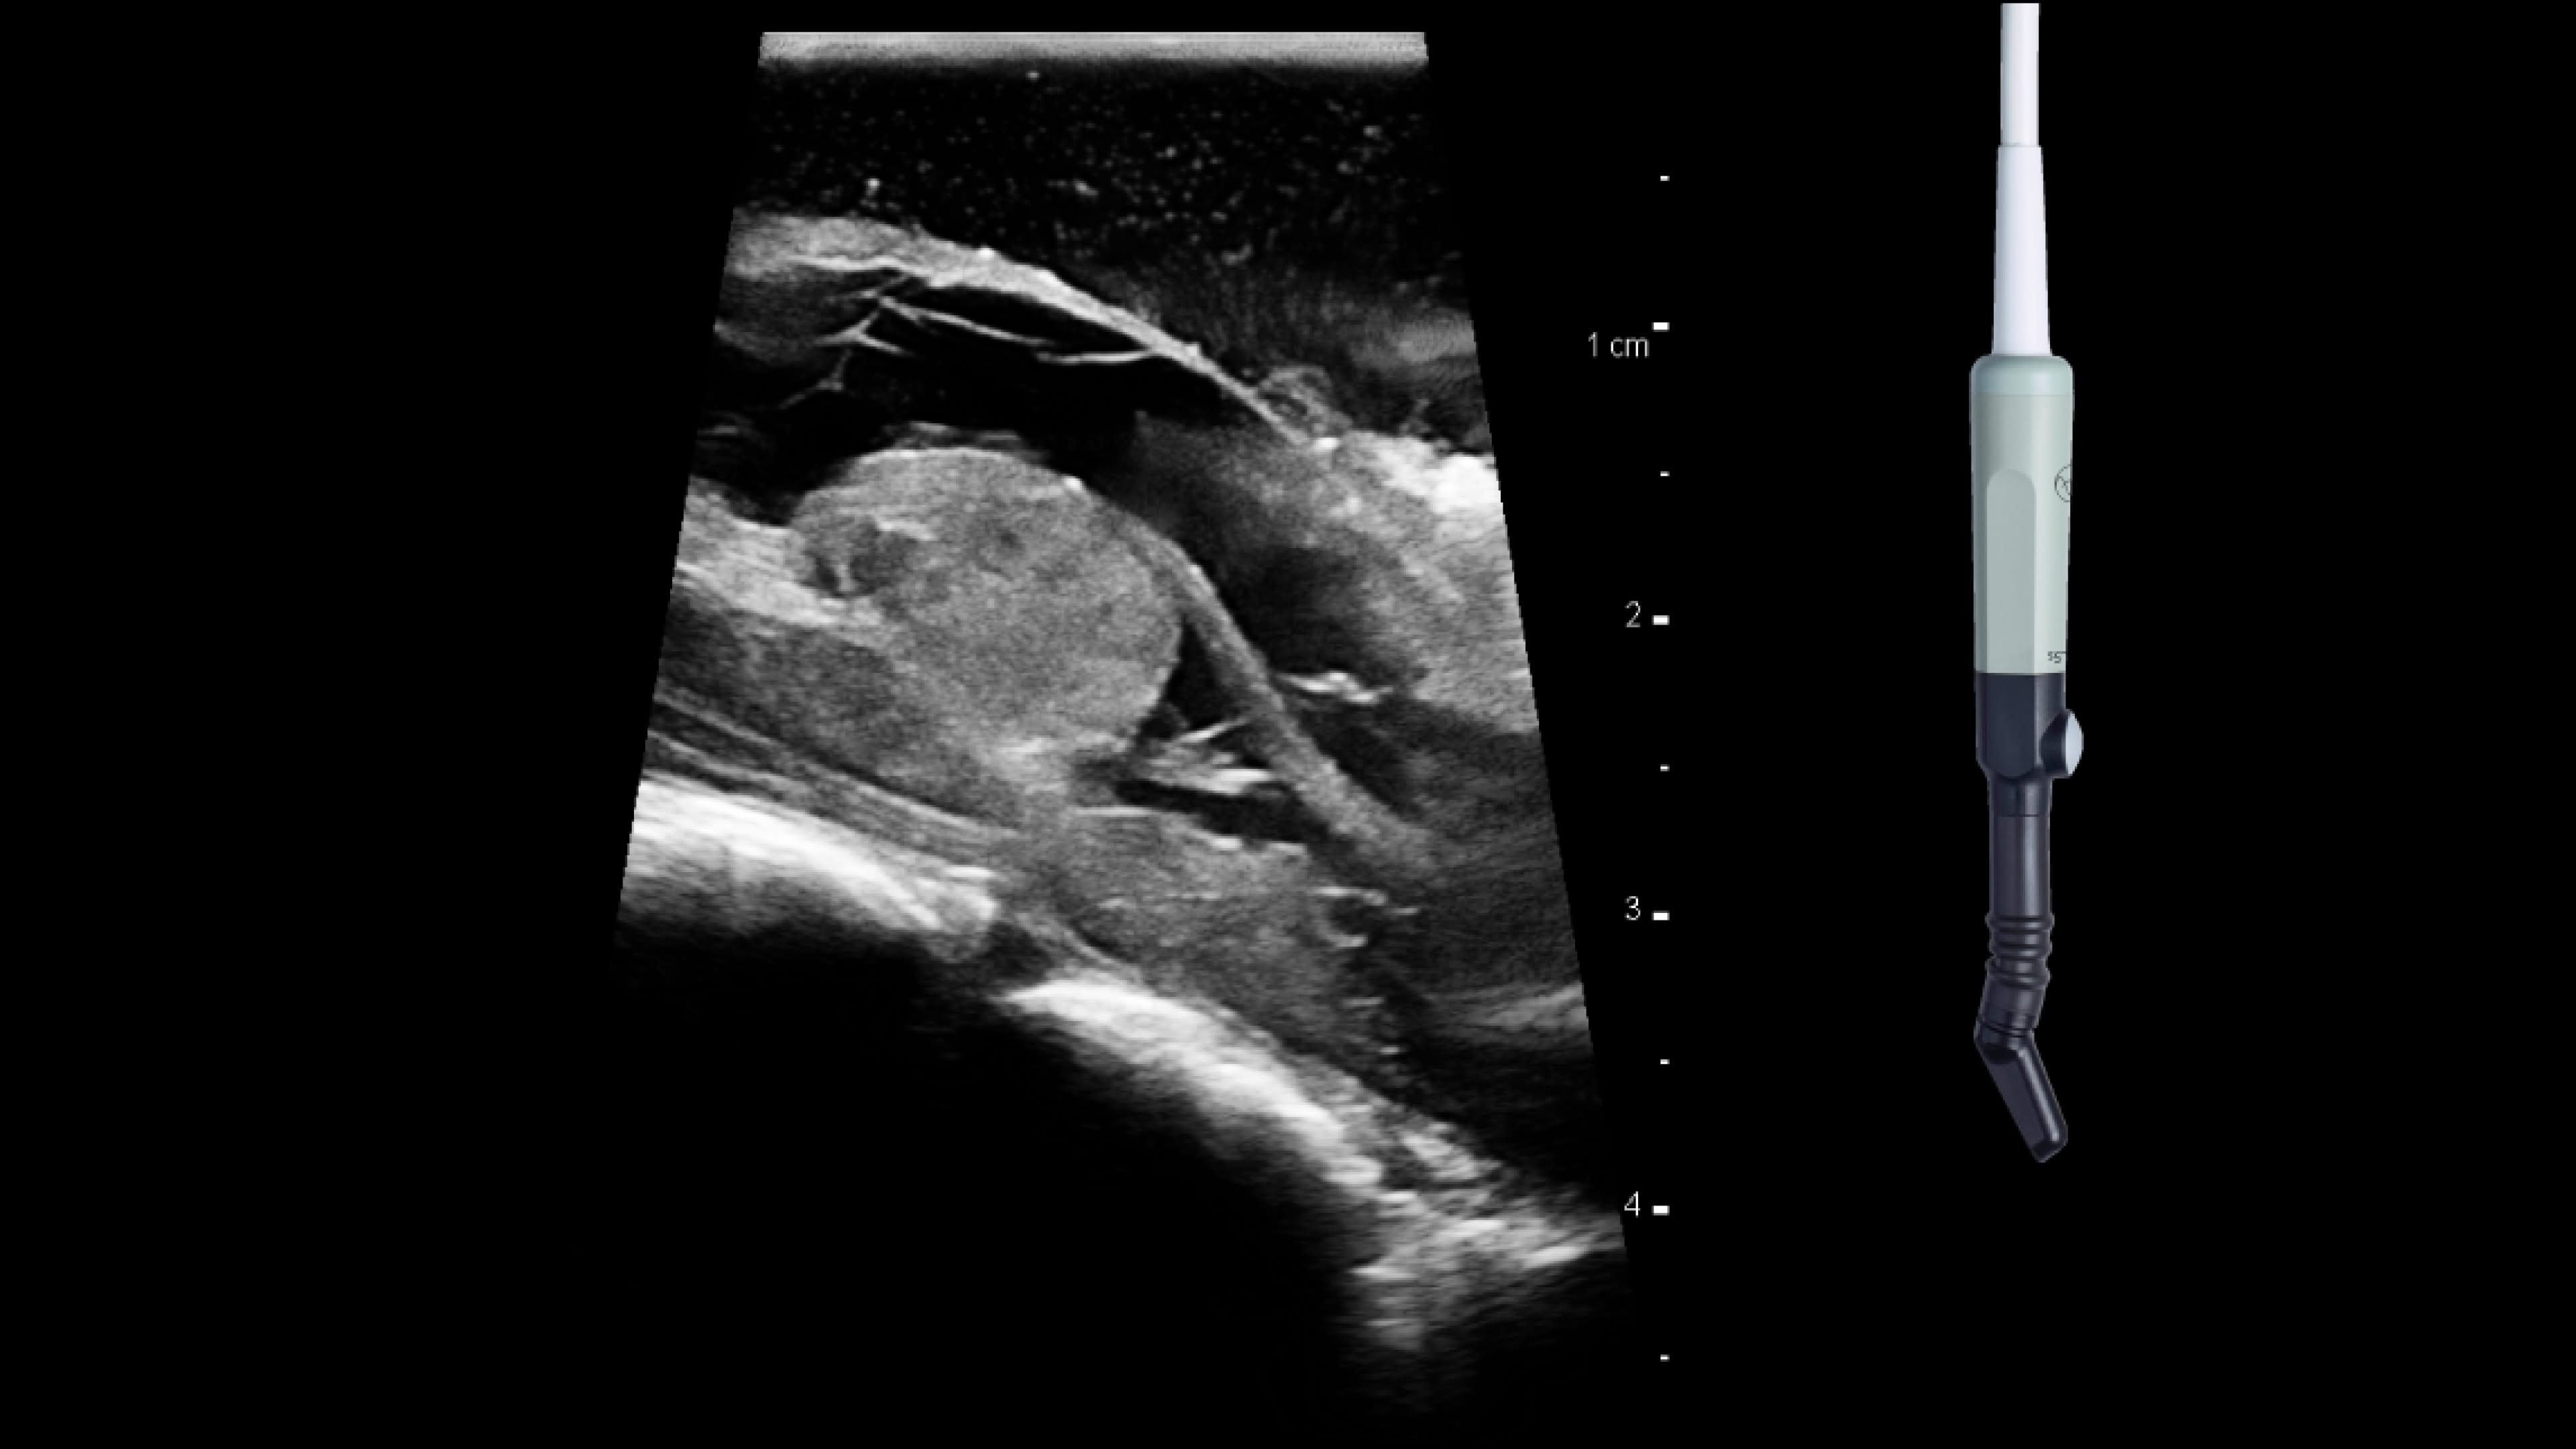

Skull base

Use intraoperative ultrasound during surgery to avoid injury by identifying blood vessels near the pituitary gland, access hard-to-reach areas and use through cranial endoports. With the bkPortfolio's smallest transducer monitor resection progress and assess for residual tumor.